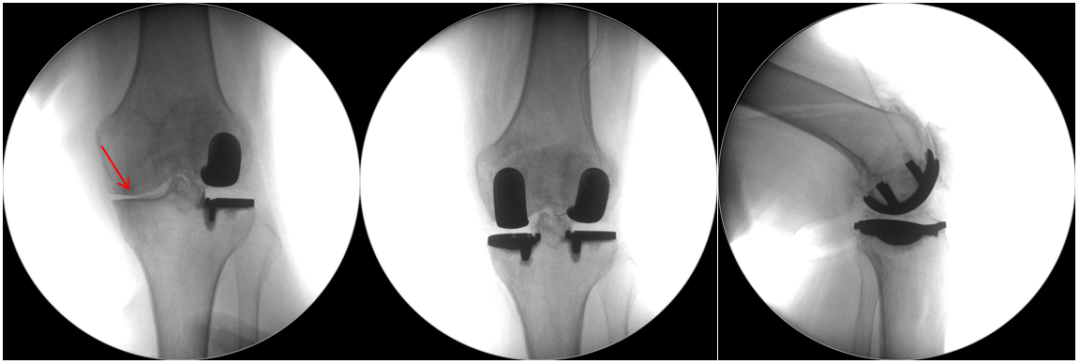

五、一期双单髁置换LINK:registered: SLED假体位置

双间室OA行Bi-UKA

正位片标准胫骨和股骨假体位置

AP位假体位置:内侧和外侧单髁分别按照各自的手术原则独立开展,假体的位置也按照各自的标准进行考量,需要综合考量的是胫股角,关节线,中央髁间隆突。

侧位片标准胫骨和股骨假体位置

侧位假体位置:内侧和外侧单髁分别按照各自的手术原则独立开展,假体的位置也按照各自的标准进行考量。

双间室OA行Bi-UKA术后内侧假体周围骨折ORIF